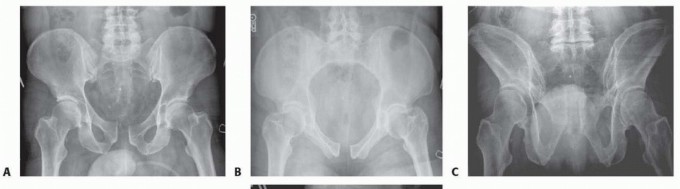

### FIG 1 • A. View of the anterior pelvis demonstrating the fibrocartilaginous disc between the pubic bodies, the superior and inferior arcuate ligaments, and the relationship between the symphysis and the pubic tubercles. B. The corona mortis is demonstrated on the inside of the superior pubic rami about 6 cm from the symphysis. It represents the anastomosis of the obturator artery and the external iliac artery. The arcuate ligaments are the main soft tissue stabilizers of the anterior pelvis. These ligaments arc both superiorly and inferiorly and are firmly attached to the pubic rami. The sacrospinous and sacrotuberous ligaments play an important role in the stability of pelvic fractures. These ligaments connect the sacrum to the ilium via the ischial spine and the ischial tuberosity. The sacrospinous ligament resists the rotational forces of the hemipelvis, and the sacrotu berous ligament prevents rotation as

well as translation of the hemipelvis. 13

If these ligaments and the pelvic floor are torn in conjunction with a pelvic fracture, symphyseal widening is more significant (see Cha 33).5 ## PATHOGENESIS The Young and Burgess classification describes the injury by the type of force acting on the pelvis. Symphyseal diastasis is most commonly seen in APC injuries or open book pelvis injuries. In APC injuries, minor widening of the symphysis may not involve disruption of the pelvic floor, including the sacrospinous ligaments. In cadaver pelvis, where the symphysis and sacrospinous ligaments were sectioned, more than 2.5 cm of symphyseal widening was observed, thus defining a rotationally unstable pelvis. 12 If the pelvic floor and the sacrospinous ligaments are torn, the involved hemipelvis can externally rotate down and out, rotating on the intact posterior sacroiliac ligaments and creating an unstable pelvis ( FIG 3).5 327

### FIG 2 • Examples of the anatomic variants between genders. The female pelvis has a more concave shape to the ring and the pubic arch has less of an acute angle because of the broader pubic body, as demonstrated in the inlet (A) and outlet (B) views of a female pelvis. The male pelvic ring is more oval, with a much more acute angle anteriorly because of the thinner pubic body, as seen the corresponding inlet (C) and outlet (D) views. Occasionally, lateral compression injuries involve fractures of the pubic rami and a symphyseal disruption. This occurs when the compressed hemipelvis causes the contralateral rami to fracture and the contralateral symphyseal body to tilt inferiorly. Because one side of the symphysis is off and can compress the bladder or uterus, altering the pelvic ring, it should be reduced to the other pubic body, which remains intact.